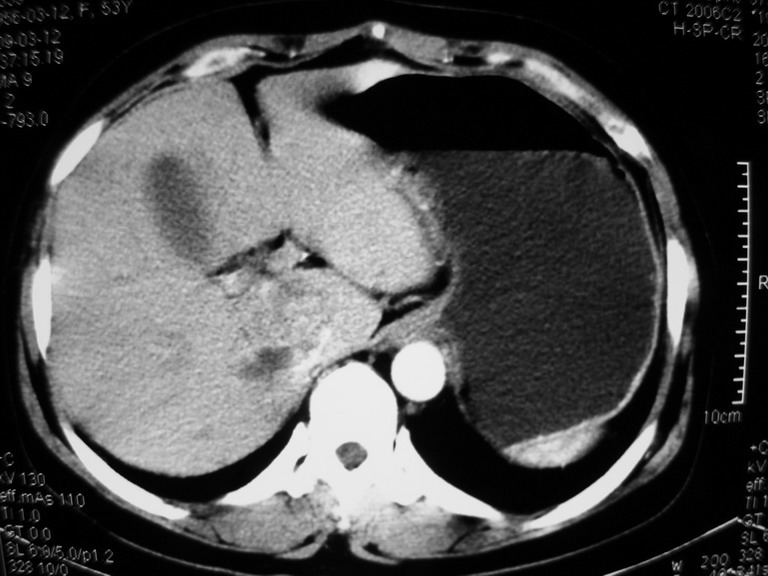

患者,女性50岁,上腹部不适2年余,既往多次腹部彩超未见异常,今日上午在我院查彩超发现肝右叶囊实性病变,外院辅助检查,afp,cea,ca199, 都在正常范围内,无肝炎史否认肿瘤史,生活在牧区

接着往下一贴看,有静脉期和延迟期,在看看和下腔静脉及十二指肠的关系,腔静脉内是不是栓子?

考虑肝右叶与尾叶交界区肝癌(部分外生),侵犯下腔静脉并下腔静脉瘤栓形成。

肝包虫病可能性大